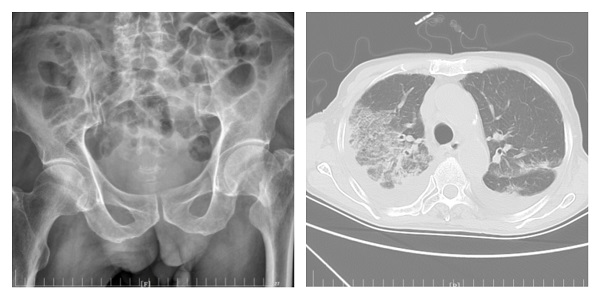

高齡老年人多存在骨質(zhì)疏松,不慎跌倒骨折后影響行走,長(zhǎng)期臥床極易并發(fā)肺部感染,如再新冠病毒感染,給治療帶來(lái)了巨大挑戰(zhàn)。12月初以來(lái),二一五醫(yī)院骨五科陸續(xù)收治了多名骨折合并新冠高齡患者,經(jīng)全院多科室通力合作...